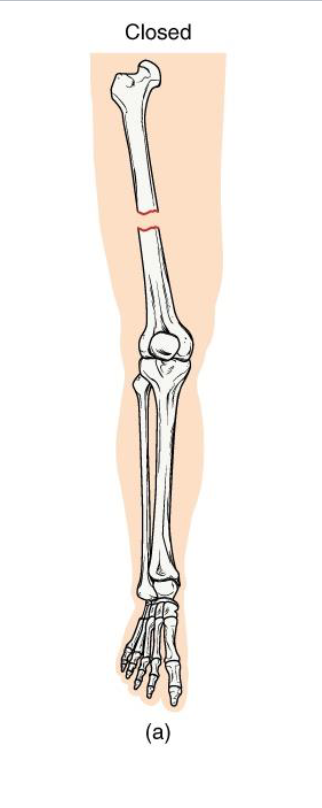

Closed Fracture

<p><strong>Definition</strong>: Bone breaks but <strong>does not penetrate the skin</strong></p><p><strong>Mechanism: Usually caused by a direct blow or bending stress</strong></p><p><strong>Clinical note: Lower infection risk;</strong> easier to manage if aligned</p><p><strong>Key Concept</strong>: Skin remains intact → internal healing environment protected</p>